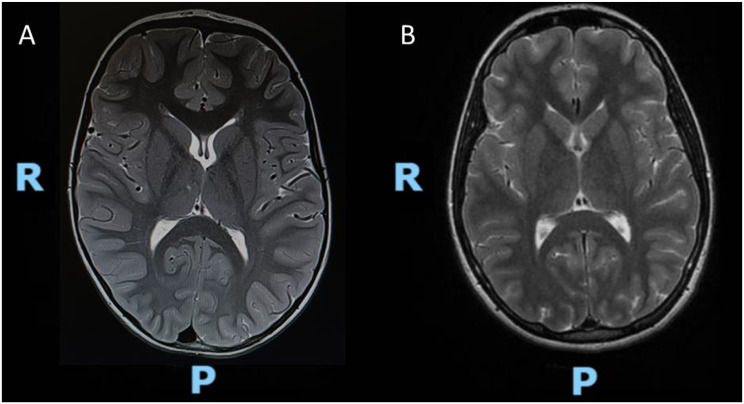

Results: We report a 12-year-old girl affected by epilepsy and learning disorders. At the age of five, she presented convulsive status epilepticus with respiratory failure at onset and she started anticonvulsant therapy with Levetiracetam with a significant improvement. Genetic analysis revealed a de novo heterozygous missense variant of PPP5C gene (c.202 C > T: p.Arg68Cys), which had not been previously described in the literature.